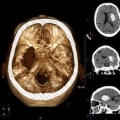

ДИАГНОСТИКА

Провести клиническое обследование (анамнез и неврологический осмотр). Достоверная диагностика кровоизлияния в мозг возможна на основании КТ или МРТ томографии. При отсутствии возможности проведения этих методов, диагностика менее достоверна и является результатом анализа клинической картины, данных спинномозговой пункции (в ликворе присутствует кровь), эхоэнцефалоскопии, дуплексного сканирования и церебральной ангиографии. Также необходимо исследовать: электролиты сыворотки крови, показатели функции почек, ЭКГ, маркеры ишемии миокарда, клинический анализ крови, протромбиновый индекс, насыщение крови кислородом.

Медицинские процедуры, проводимые при заболевании внутримозговое кровоизлияние: КТ головного мозга (КПП) сканирование без красителей, Магнитно-резонансная томография, Спинальная пункция, Эхоэнцефалография, Дуплексное сканирование брахиоцефальных артерий (БЦА), Ангиография, Биохимический анализ крови, ЭКГ, Клинический анализ крови, Протромбиновое время, Протромбиновый индекс, Исследование газов крови